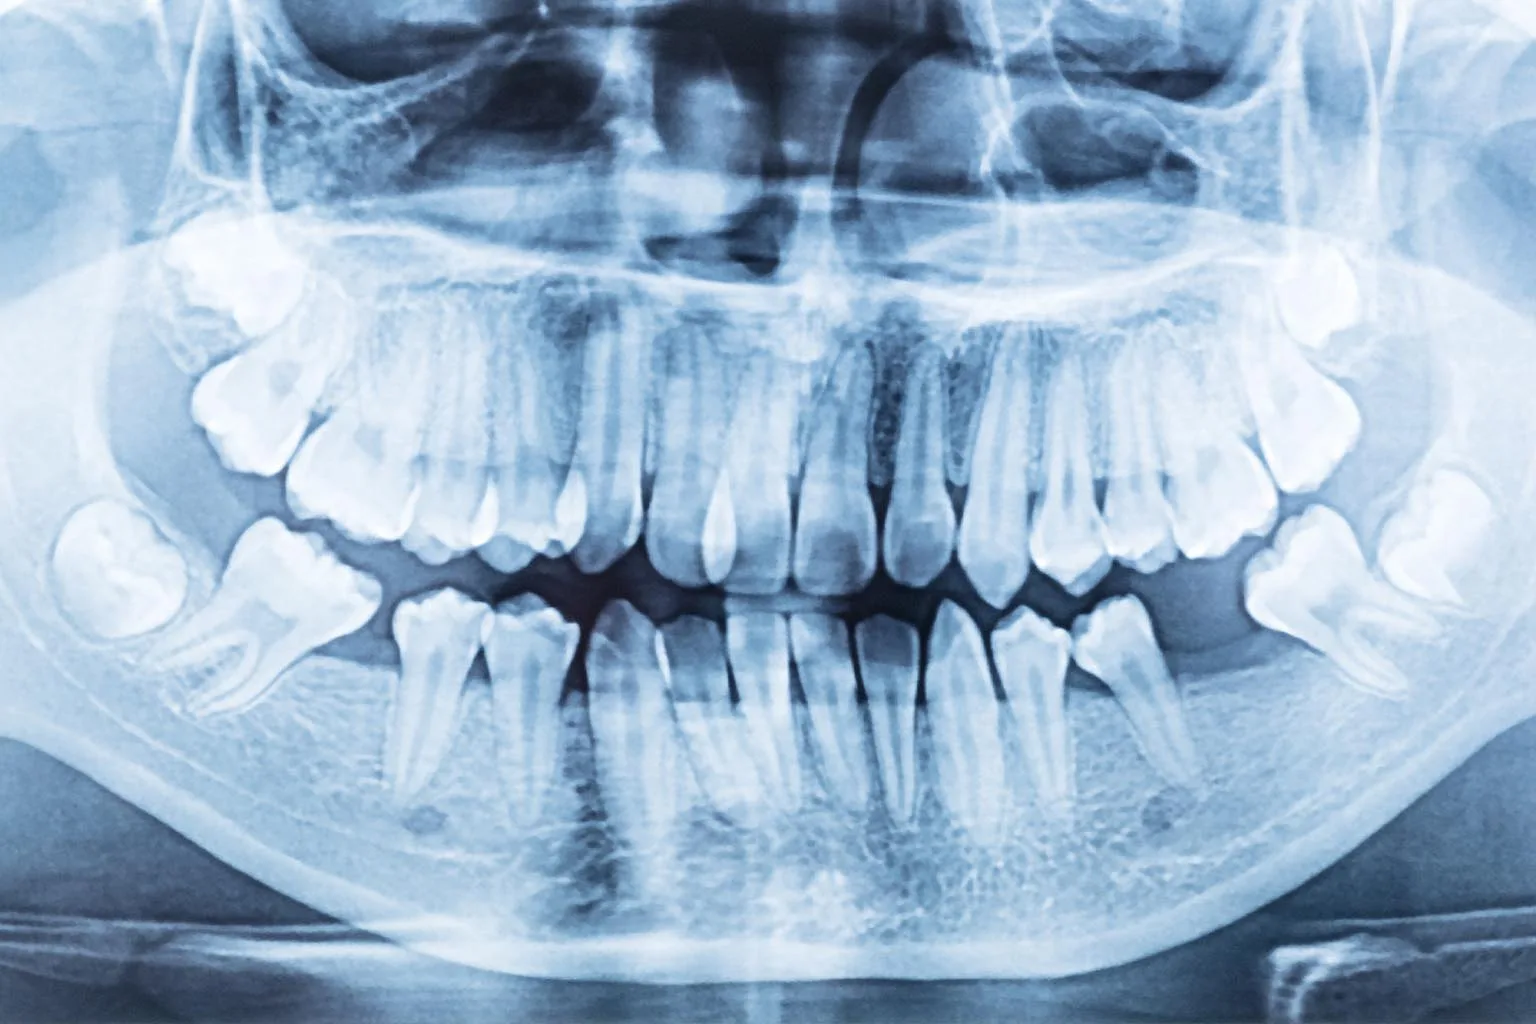

Protinio danties dygimas visada daugiau ar mažiau skausmingas, nes dygstančiam dančiui reikia prasikalti pro storas dantenas. Protiniai dantys gali ir visai neišdygti. Visiškai susiformavę, bet neišdygę dantys vadinami retinuotais dantimis ir žmogui paprastai netrukdo, jie yra matomi tik rentgeno nuotraukose.

Odontologai rekomenduoja kreivus protinius dantis šalinti kuo greičiau. Ar dantį šalinti, ar jį palikti, galima pasakyti tik padarius rentgeno nuotrauką. Jei aplink dantį formuojasi apnašos, jis nepilnai išdygęs, formuojasi aplink jį esančių audinių uždegimas, cistos, tuomet delsti nebėra ko, tačiau kiekvieną atvejį gydytojas su pacientu aptaria individualiai ir tik po išsamios apžiūros ir tyrimo.

Prieš procedūrą atliekamas rentgenologinis tyrimas – panoraminė rentgeno nuotrauka, sudėtingesniais atvejais – kompiuterinė tomografija, kad būtų galima tiksliai įvertinti dantų padėtį ir suplanuoti saugią operaciją.